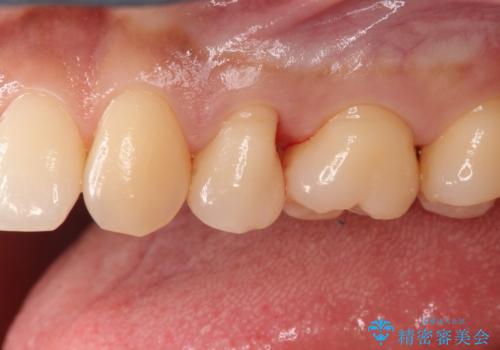

適合の良いセラミックインレー

e-max プレスインレーにて修復治療を行っているため適合性及び審美性の高い治療を行うことができます